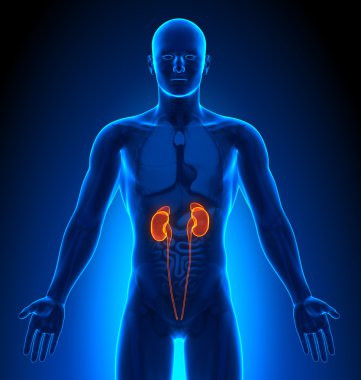

İnsan vücudundaki böbreklerin hologramı. Geleceğin sağlık hizmetleri. Modern tıp bilimi. 3B illüstrasyon, 3B canlandırma

ArkaplanresimlemeİnsanSağlıksağlıklıİlaçSağlık hizmetleriHastalıkTıbbidikkatteknolojiçizgi filmGeleceğe yönelikDoktorHastaneAygıtDijitalgövdeterapiTedavibiyolojiBilimkanserSistemGözlüklerAcıYenilikorgKulaklıktaşlaranatomiklinikİşlemOrgan nakliBöbreklerBöbrekHologramçokgenÜroloji3d oluşturma3B illüstrasyonpiyelonefritBenzer İçerikler